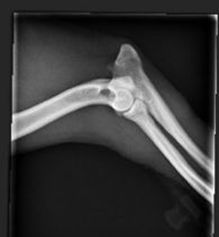

Patellaluksaatiossa polvilumpion on siirtynyt pois normaali paikastaan reisiluun pään telaurasta. Se on synnynnäinen rakennevika, joka liittyy takajalkojen anatomiaan — erityisesti suoraan polvi- ja kinnerkulmaan sekä matalaan telauraan. Patellaluksaatiota esiintyy runsaasti kääpiöroduilla, kuten havannankoiralla. Sairauden periytymistapaa ei tunneta tarkasti, mutta tietyissä suvuissa alttius näyttää olevan suurempi kuin toisissa. Pienillä roduilla patella siirtyy useimmiten sisäsivulle (mediaalinen luksaatiotyyppi).

Miten patellaluksaatio todetaan?

Patellaluksaatio voidaan todeta eläinlääkärin tekemässä polvitutkimuksessa. Tutkimus tehdään koiran seistessä, ilman rauhoitusta. Eläinlääkäri tutkii käsin, miten helposti polvilumpio siirtyy pois paikaltaan. Lausunto annetaan asteikolla 0–4, jossa 0 tarkoittaa normaalia polvea ja 4 vakavinta muotoa, jossa lumpio on pysyvästi pois paikoiltaan.

Virallinen polvitutkimus voidaan tehdä havannankoiralle 12 kuukauden iästä alkaen, mutta lopullinen tulos tulee vasta 3 vuoden iässä. Tutkimuksen voi tehdä vain siihen koulutettu eläinlääkäri. Tarkista eläinlääkärit: